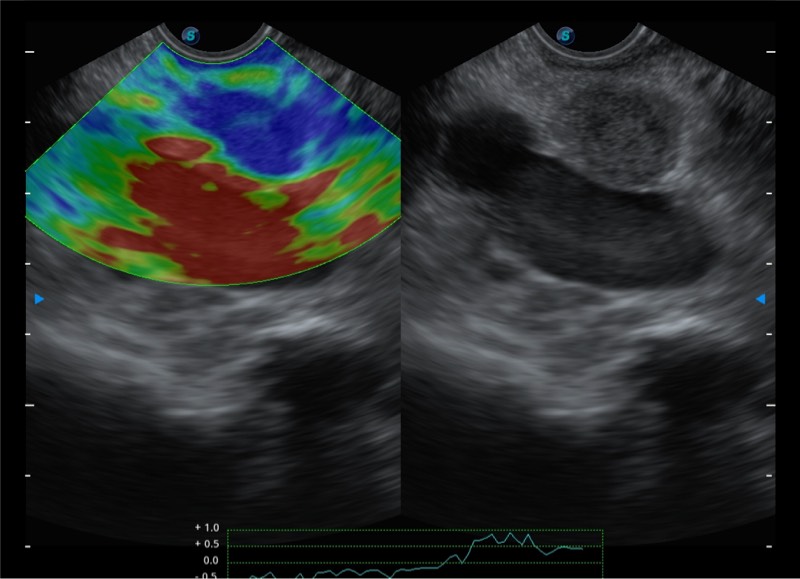

基于二十年的超声技术积累,16877太阳集团提供了最新一代的独立超声主机,在提供高质量图像的同时满足多学科使用。具备常见多普勒技术并提供弹性成像、声学造影等高端影像技术。新一代传感器具有更强的抗干扰能力并减少图像伪影。

4-12MHZ宽频输出